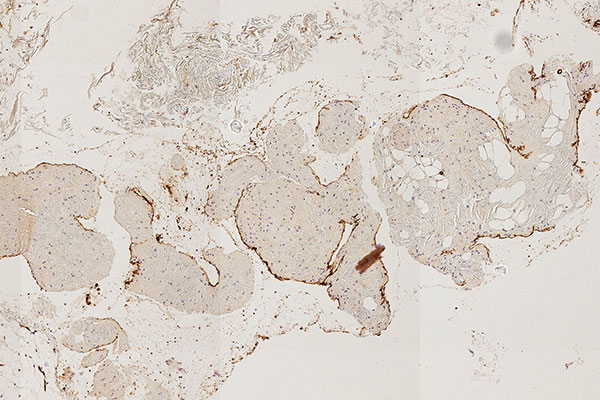

Histopathological section; CD31 stain for specific staining of vascular endothelial cells, which then stain dark brown. 80x magnification of the punch cylinder. This proves that the outer cellular boundary of the visible lesion corresponds to blood vessel endothelia.